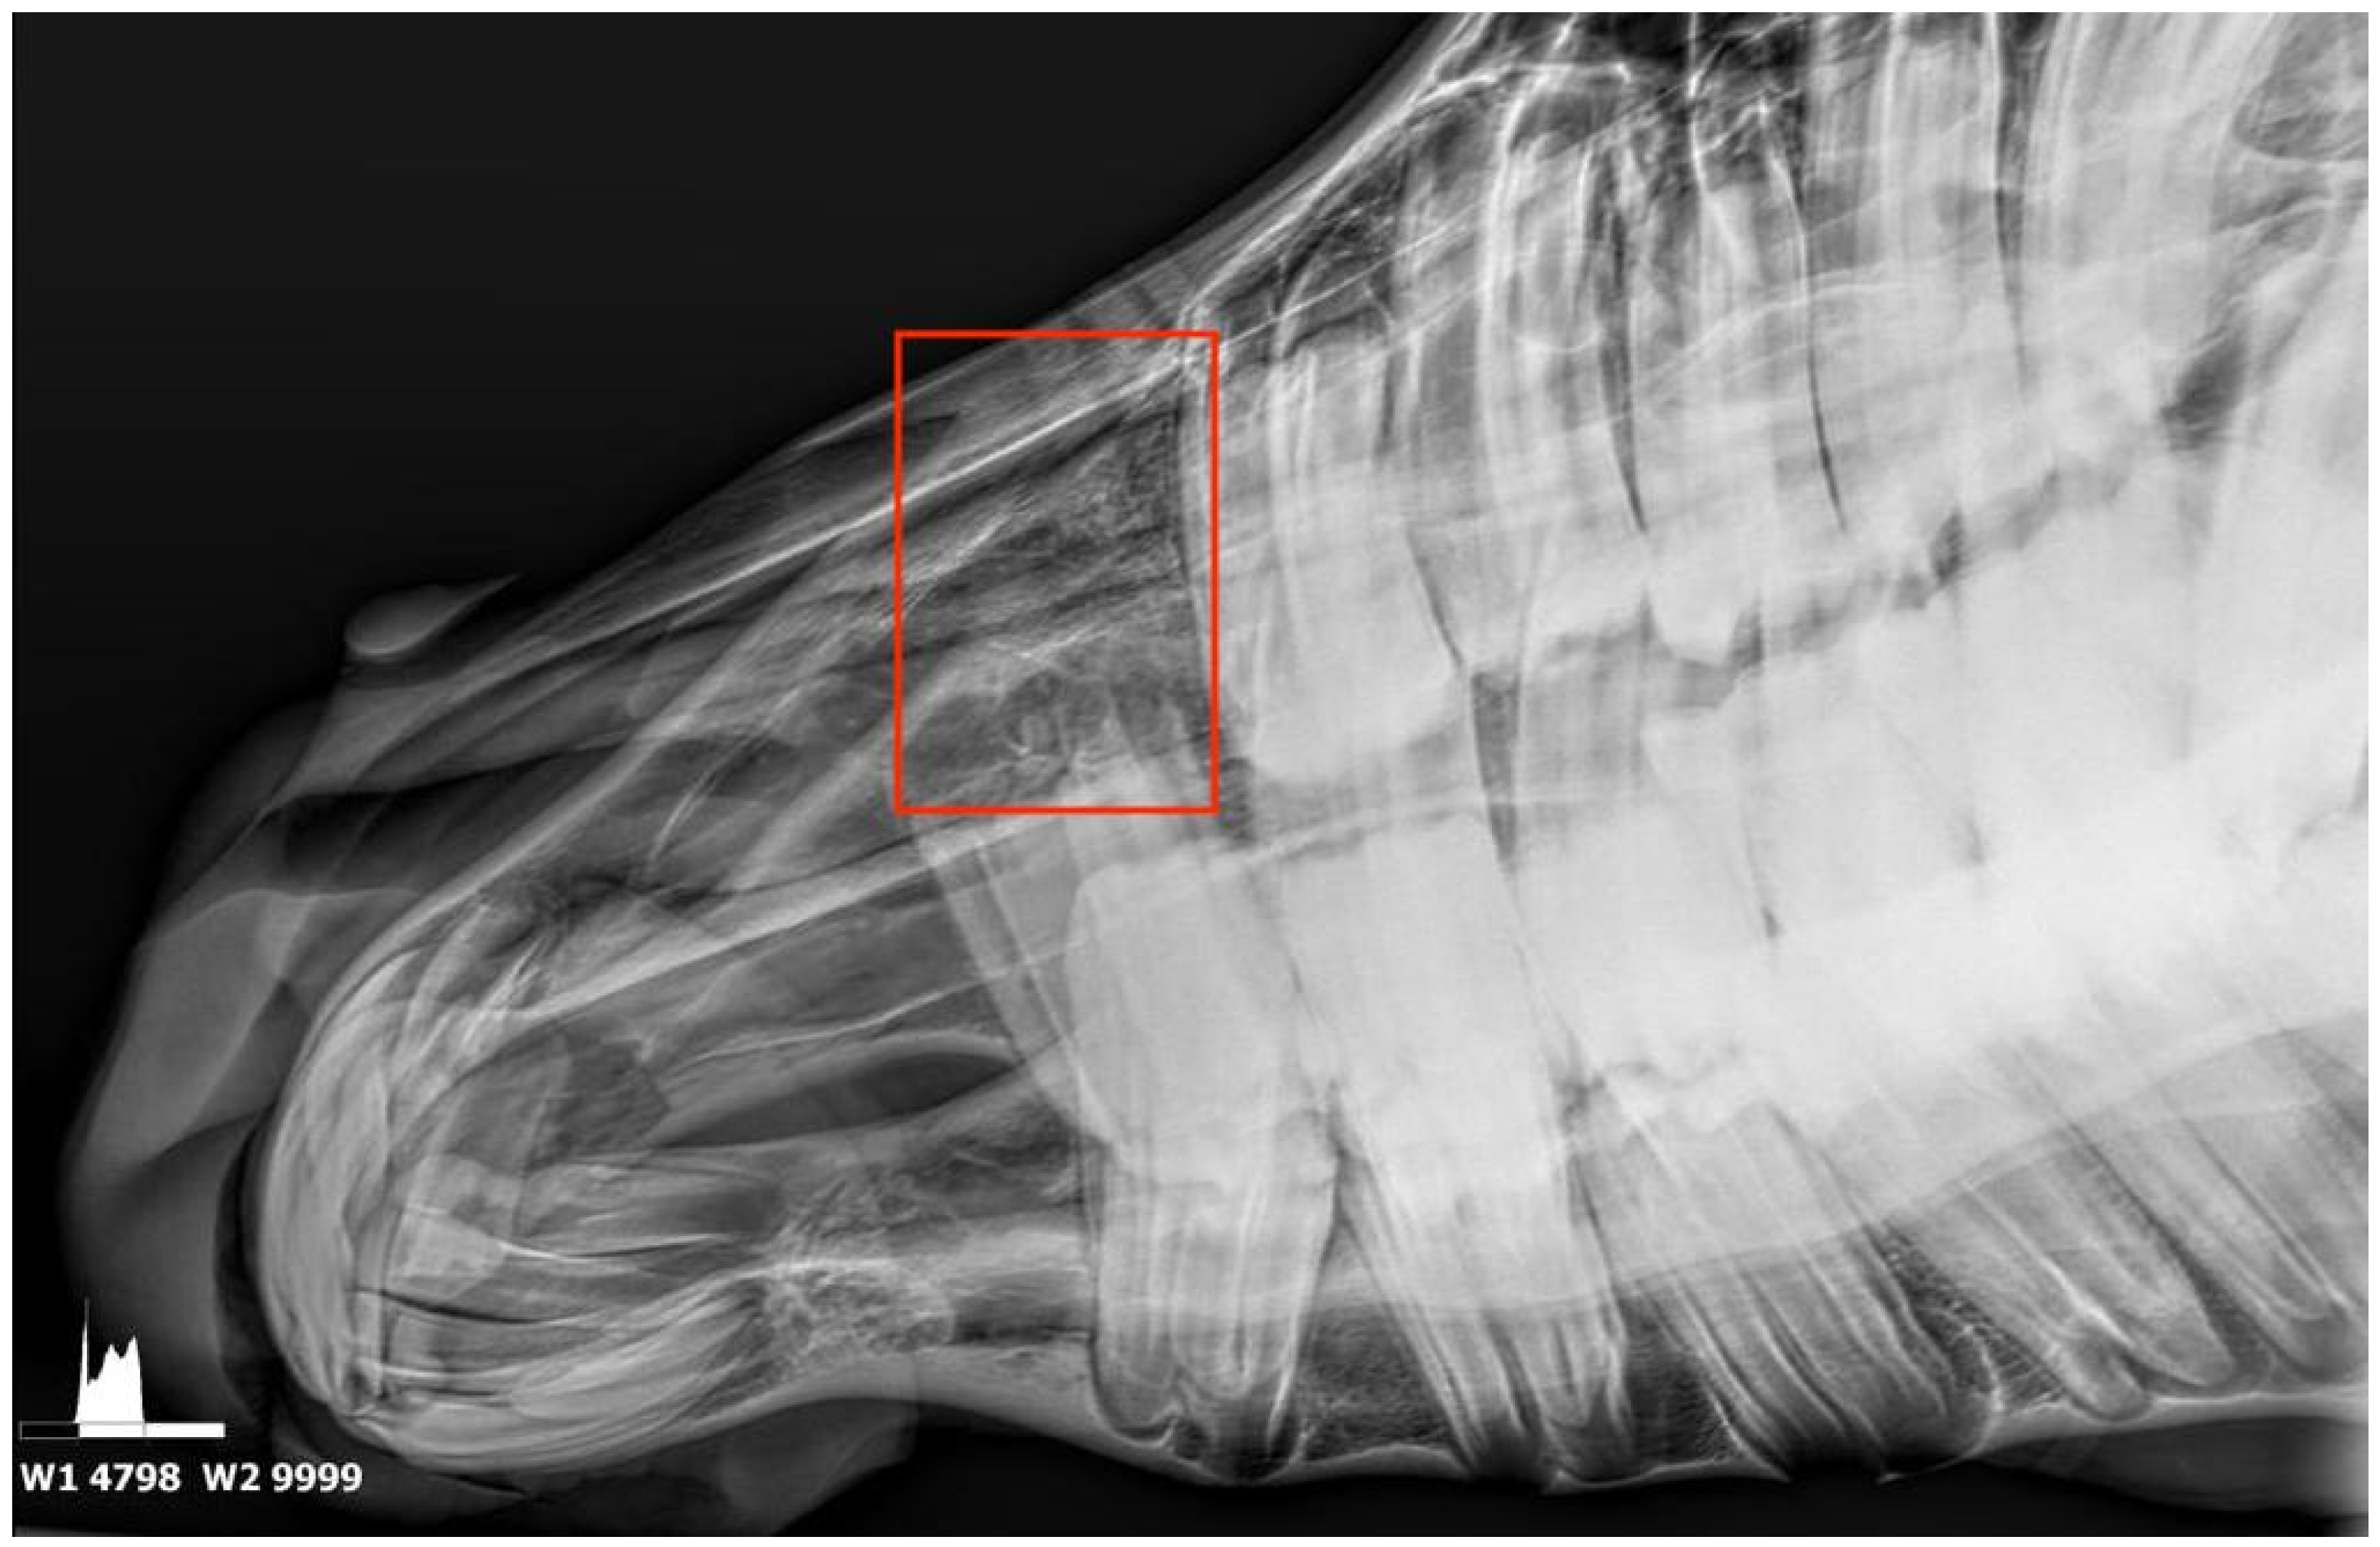

2.2. Diagnostic Imaging